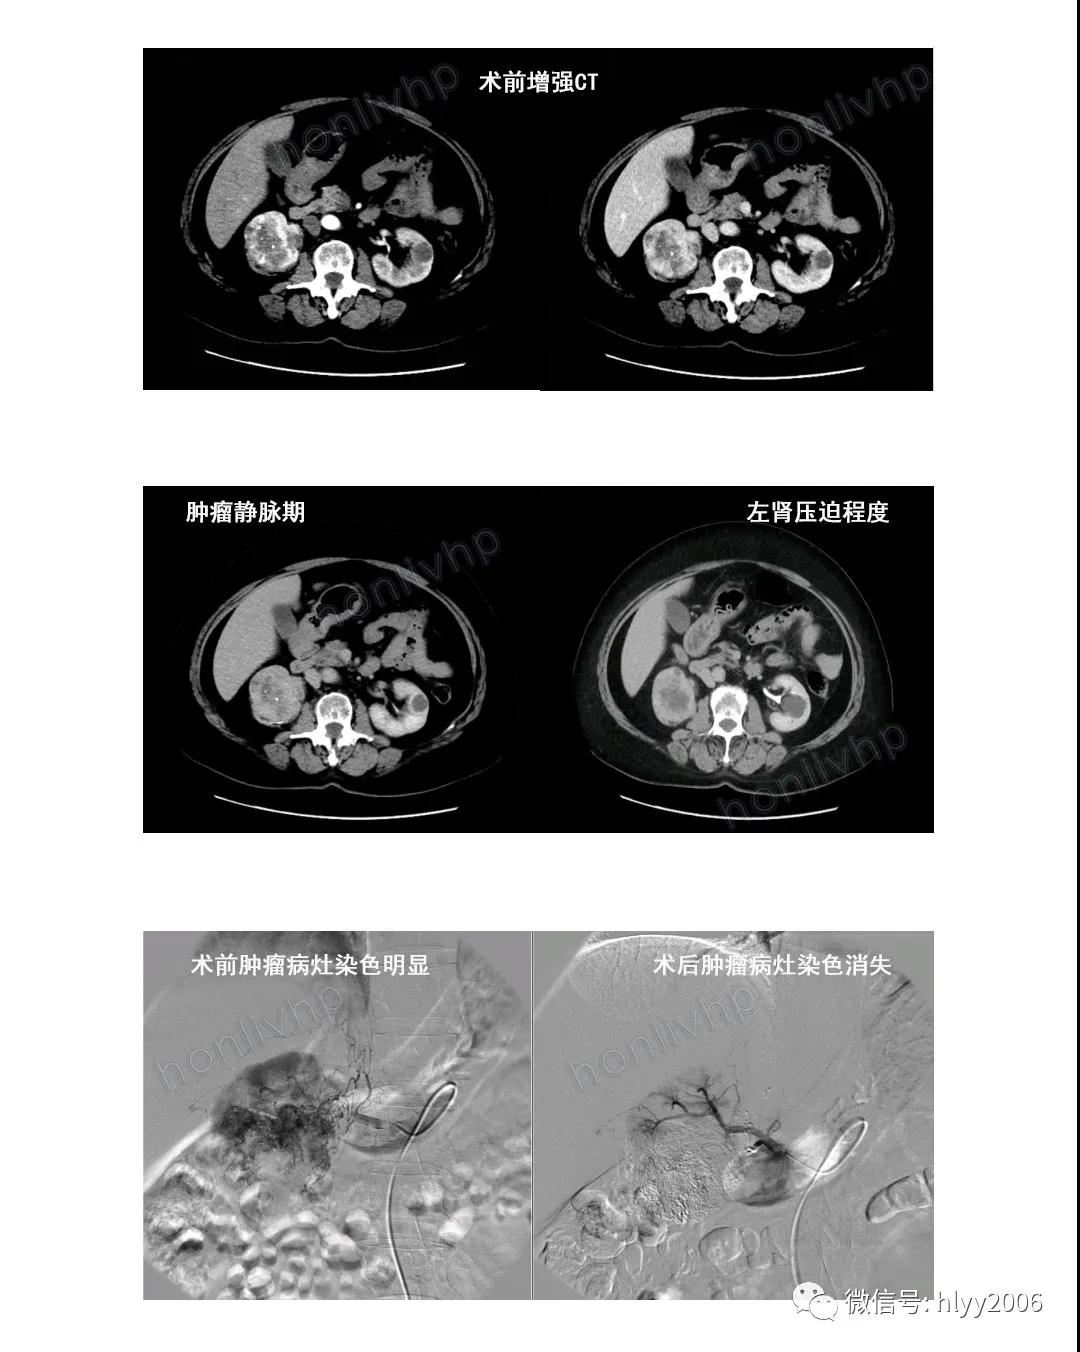

為腎癌患者實施“經(jīng)皮右腎動脈灌注化療+栓塞術(shù)”

河南宏力醫(yī)院介入科副主任醫(yī)師龍軍強接診后,詳細詢問病史,建議住院治療。結(jié)合患者各項輔助檢查結(jié)果及臨床體征,患者符合“經(jīng)皮右腎動脈灌注化療+栓塞術(shù)”的適應(yīng)癥。

在介入科醫(yī)、護、技的通力配合下,為患者實施了經(jīng)皮右腎動脈灌注化療+栓塞術(shù)。

術(shù)后,患者在介入科醫(yī)護人員的精心治療、護理下,不適癥狀明顯好轉(zhuǎn),一周后康復(fù)出院。近日隨訪,患者對治療效果非常滿意。

經(jīng)皮腎動脈化療+栓塞使腫瘤內(nèi)藥物濃度比周圍靜脈給藥高,能明顯提高療效,減輕全身副作用,是介入放射學(xué)治療的又一重要方法。姑息性栓塞雖未手術(shù)切除腫瘤,但也可使患者全身情況改善,對于部分不能外科切除的腫瘤是一種較為有效的治療方法。